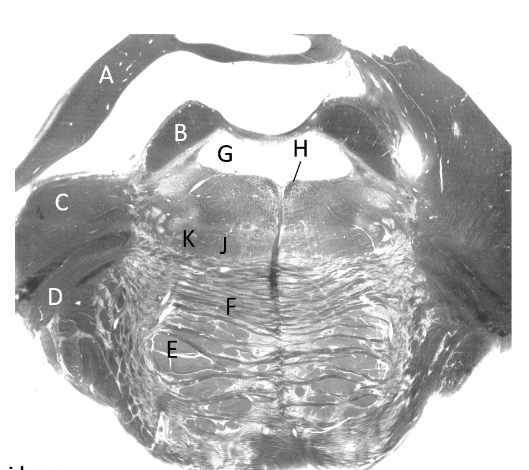

at what level is this?

mid pons

what is a?

cerebellum

what is b?

superior cerebellar peduncle

what is c?

middle cerebellar peduncle

what is d?

trigeminal nerve

what is e?

pyramidal fibres

what is f?

transverse pontine fibres

what is g?

4th ventricle

what is h?

median longitudinal fasciculus (p)

what is j?

medial lemniscus (p)

what is k?

spinothalamic tract (p)